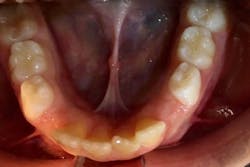

Floor of the mouth

A good time to see where the lingual frenum attaches is when you examine the floor of the mouth. Does it attach into the floor of the mouth as it should? Or do you see it attaching to the alveolar ridge? When this attachment is present, it often presents as an “Eiffel tower” appearance (figure 1). This appearance may be indicative of a posterior lingual restriction. Further functional evaluation is warranted by an orofacial myologist.